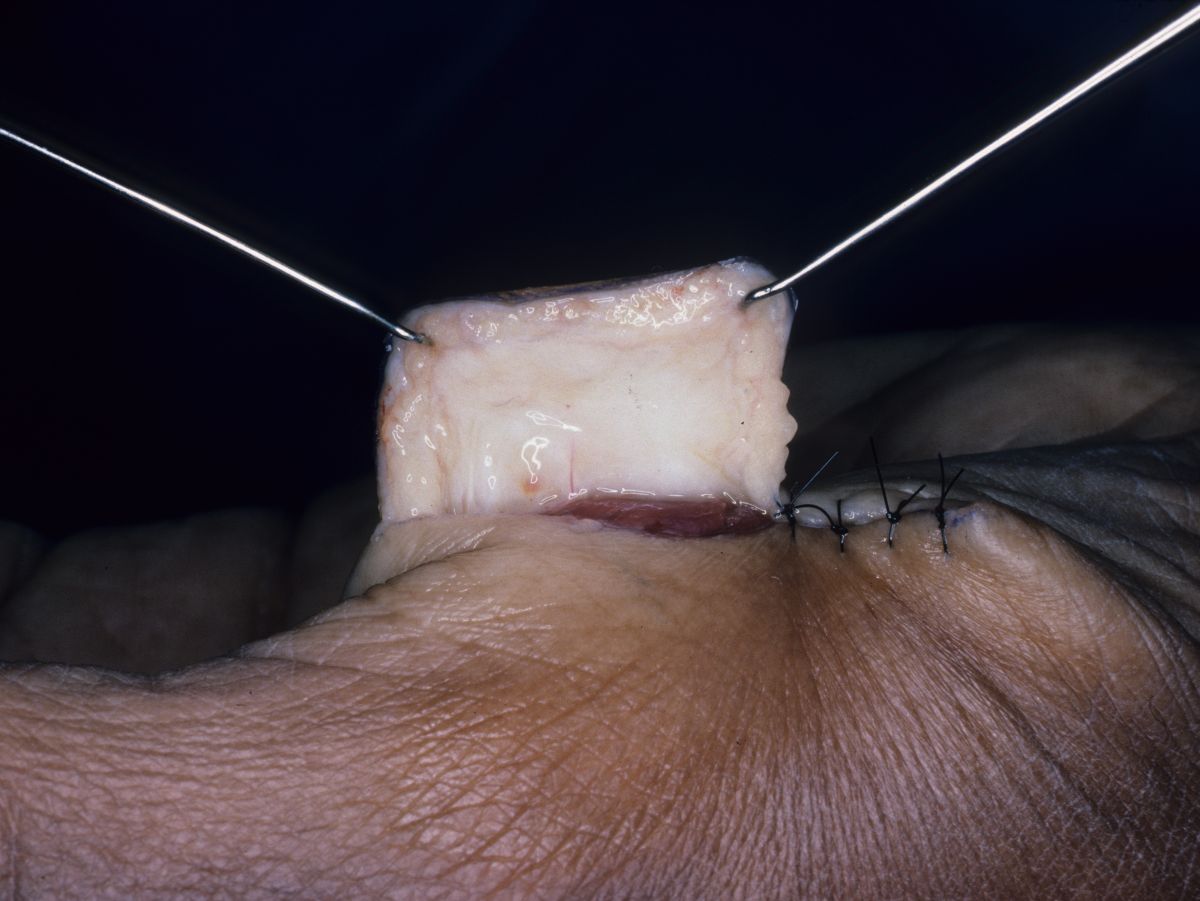

| Four corner

sutures may be all that is required. ¤ Strong (2-0 or 3-0) sutures should be used to secure these anchoring points. ¤ Avoid multiple sutures or tight closure. ¤ Avoid sutures in the base or tip of the flap - only suture the sides. ¤ The palmar finger skin edge should come to rest against the deep surface of the flap. Flap division is simpler if the palmar finger heals to the flap rather than to the donor site skin edge abutting the base of the flap. |

| Flap inset,

bringing the thumb to the finger. |

| Ideally, the flap

protrudes beyond the tip, providing extra skin which

will recontour to a rounded tip. |